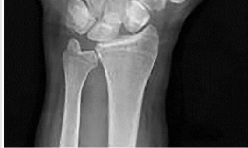

Question 11:

A 60-year-old female undergoes open reduction and internal fixation of a distal radius fracture with a volar locking plate. Three months postoperatively, she suddenly loses the ability to actively flex the interphalangeal joint of her thumb. Which technical error during the initial surgery is the most likely cause of this complication?

Correct Answer: Placement of the plate prominent to the volar watershed line

Explanation:

Attritional rupture of the flexor pollicis longus (FPL) tendon is a well-documented complication of volar locking plate fixation for distal radius fractures. It most commonly occurs when the plate is placed distal to the 'watershed line' (Soong Grade 2), causing the FPL tendon to rub directly against the prominent distal edge of the plate during wrist motion.